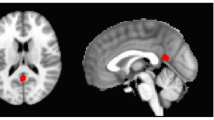

Social transmission of fear is not restricted to visual or auditory cues, but extends to the phylogenetically more ancient olfactory domain. Anxious individuals exhibit heightened sensitivity towards chemosensory stress signals in sweat; however, it is still unknown whether endogenous neuromodulators such as the peptide hormone oxytocin (OXT) influence the chemosensory communication of stress. Here, we investigated whether OXT selectively diminishes behavioral and neural responses to social chemosensory stress cues utilizing a randomized, double-blind, placebo (PLC)-controlled, within-subject functional MRI study design. Axillary sweat was obtained from 30 healthy male donors undergoing the Trier Social Stress Test (stress) and bicycle ergometer training (sport). Subsequently, 58 healthy participants (30 females) completed a forced-choice emotional face recognition task with stimuli of varying intensities (neutral to fearful) while they were exposed to both sweat stimuli and a non-social control odor following intranasal OXT or PLC administration, respectively. OXT diminished stress-induced recognition accuracy and response time biases towards fear. On the neural level, OXT reduced stress-evoked responses in the amygdala in both sexes, the anterior cingulate cortex (ACC) in females, and the hippocampus in males. Furthermore, OXT reinstated the functional connectivity between the ACC and the fusiform face area that was disrupted by stress odors under PLC. Our findings reveal a new role for OXT signaling in the modulation of chemosensory communication of stress in humans. Mechanistically, this effect appears to be rooted in a downregulation of stress-induced limbic activations and concomitant strengthening of top-down control descending from the ACC to the fusiform face area.